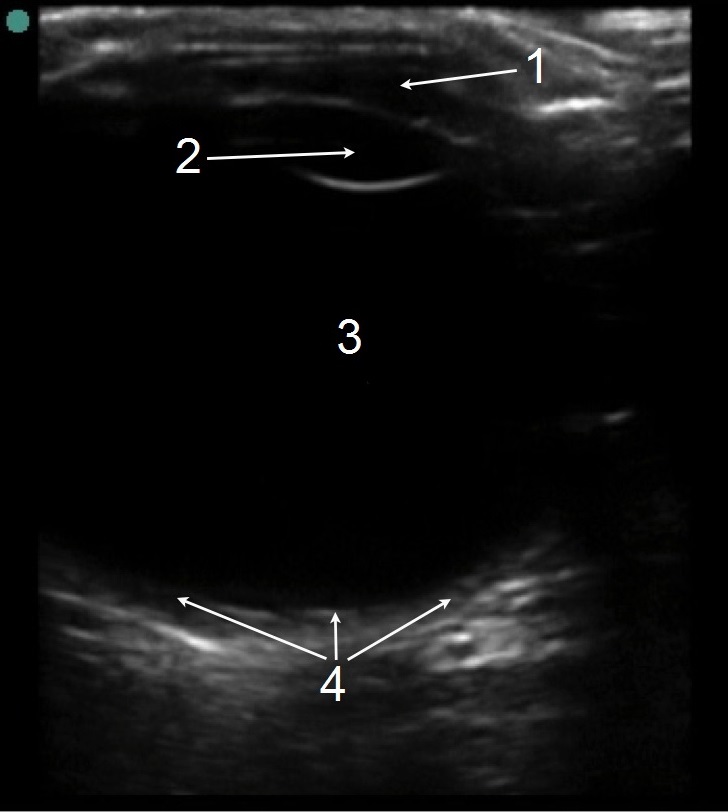

眼部正常解剖结构 3 图像

前房

晶状体

玻璃体

视网膜